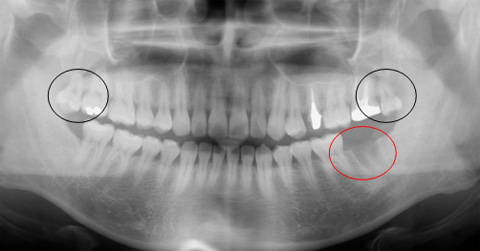

![]() |

| 初診時のレントゲン像 黒丸は不必要な親知らずです。赤丸は1週間前に抜歯した部位です。 |